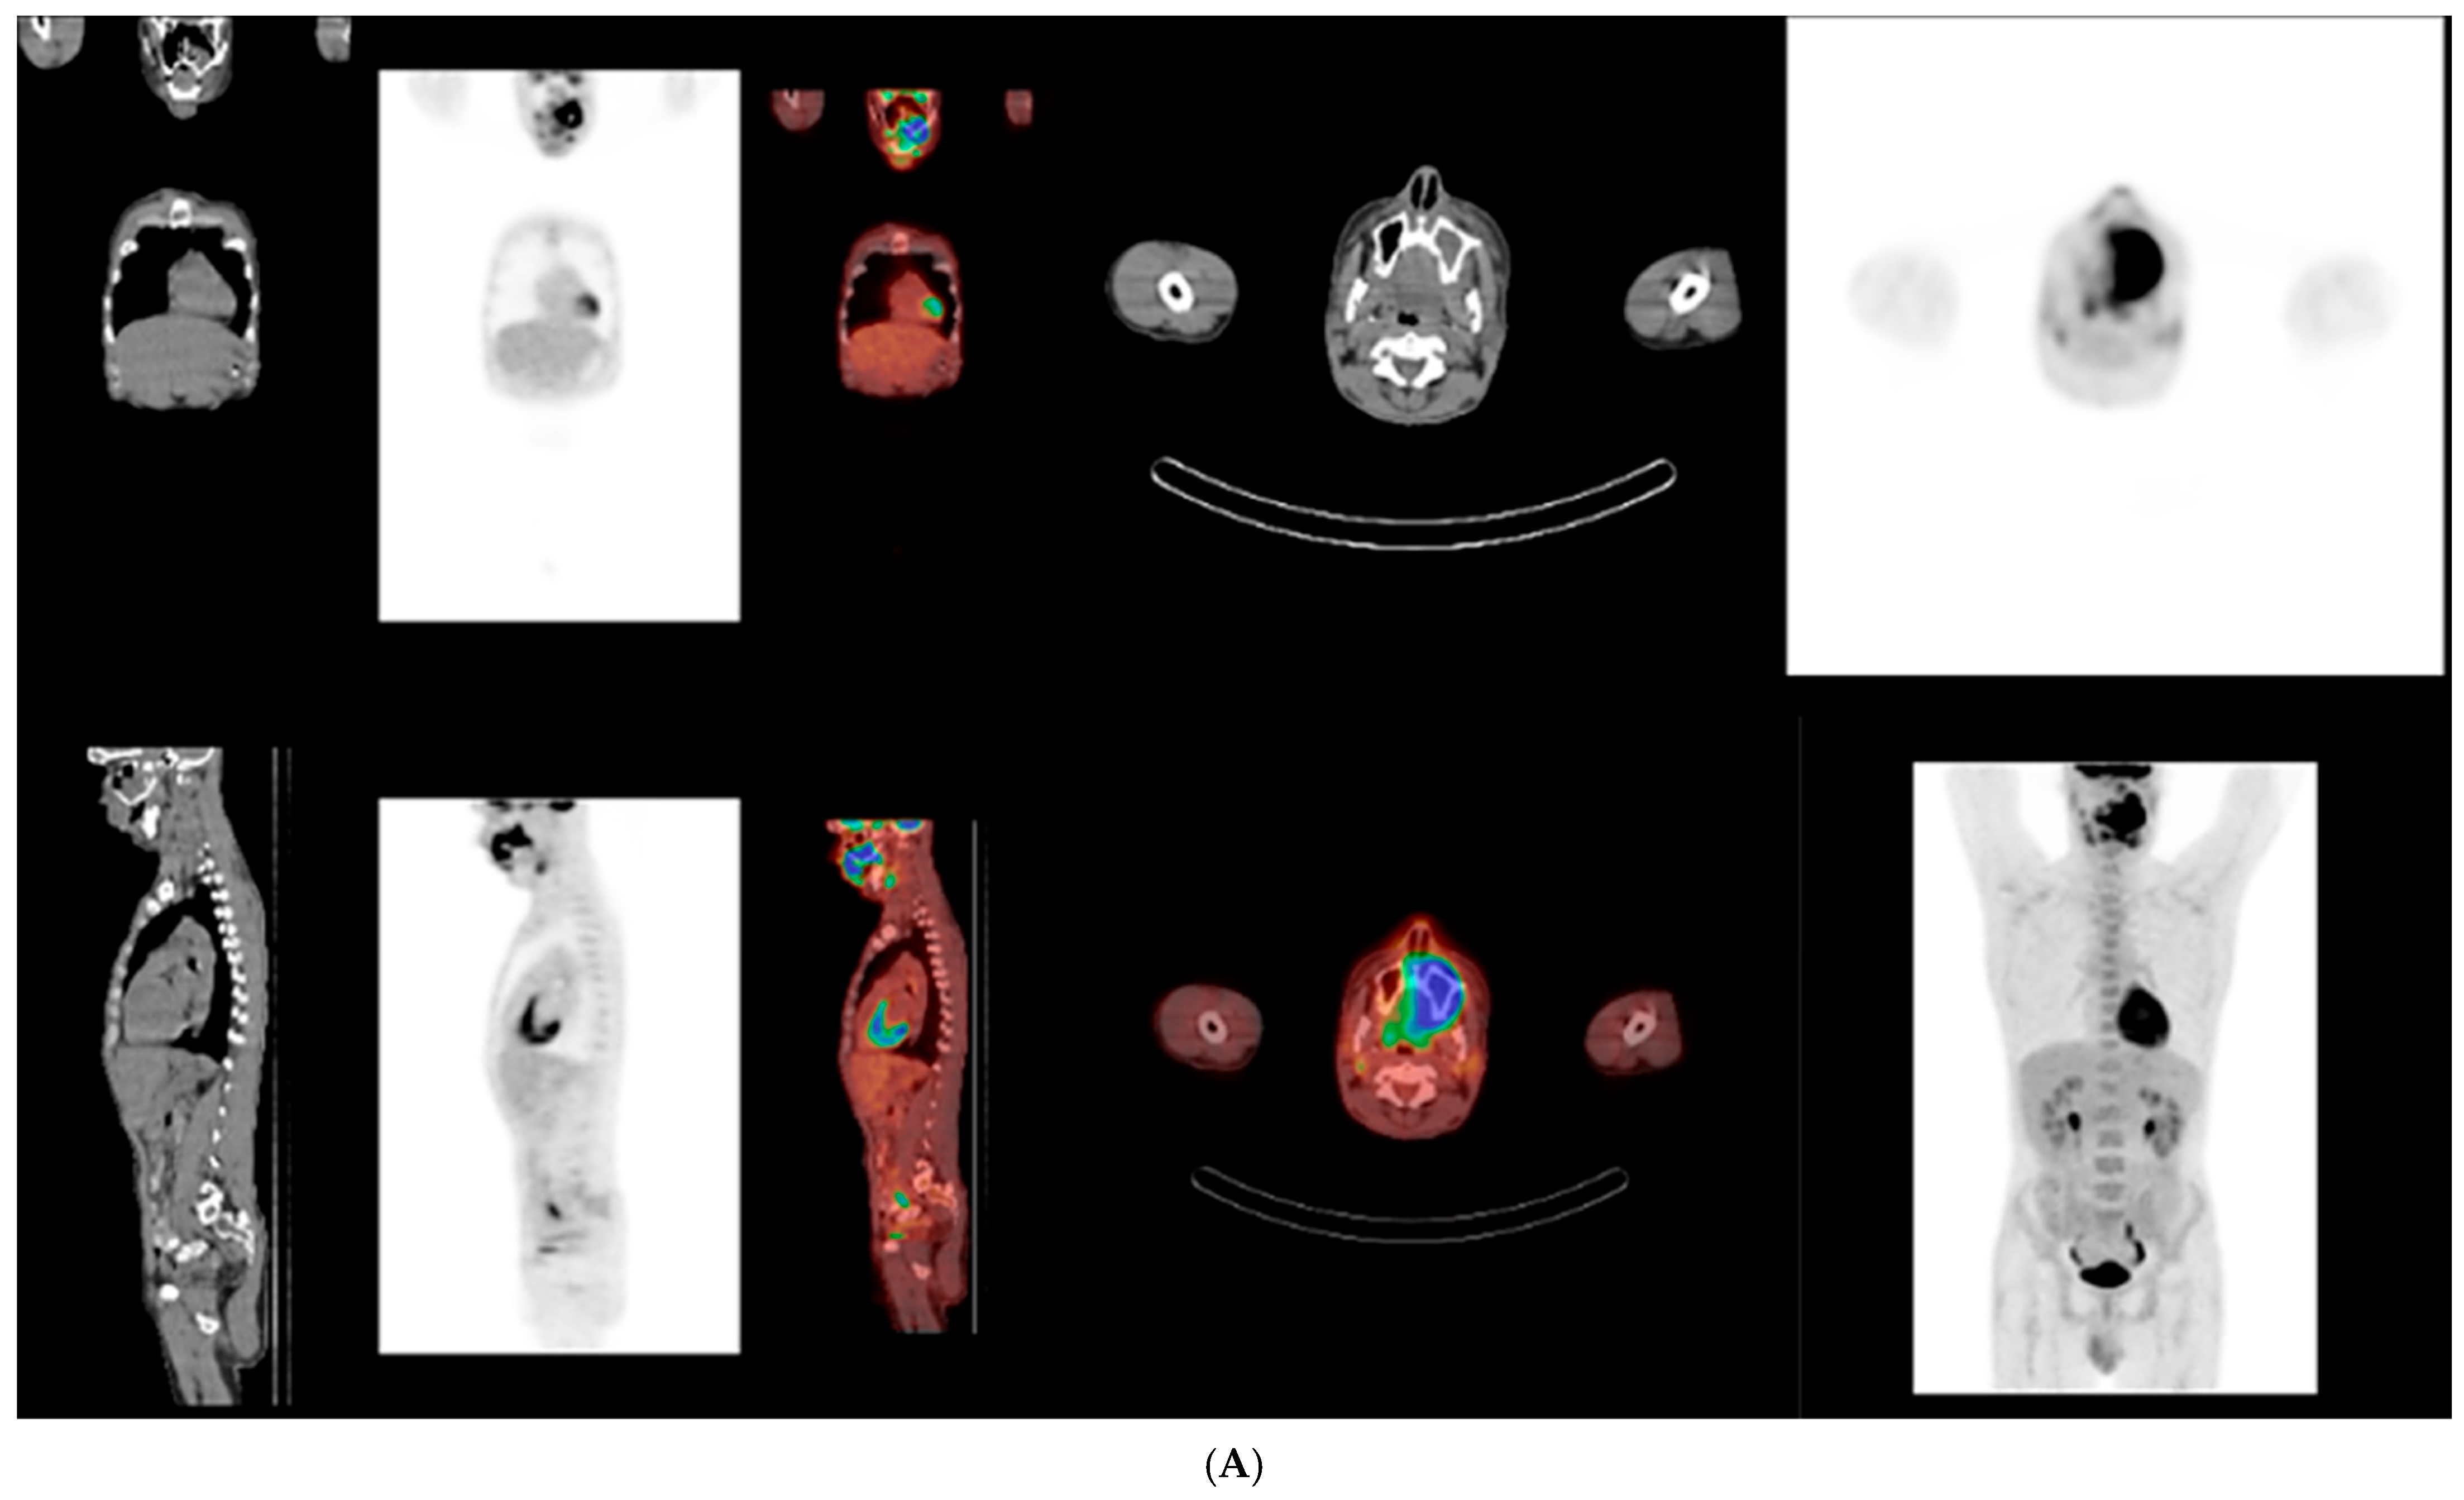

Upon referral to hematology, PET–CT imaging demonstrated a metabolically active, locally invasive lesion confined to the oral and maxillofacial region, without evidence of distant organ involvement at initial staging (Figure 4). At the time of initial presentation, imaging assessment consisted of panoramic radiography and PET-CT, which was selected as the primary modality for staging and evaluation of disease extent in this aggressive lymphoma. No dedicated thin-slice CT was performed at initial diagnosis, as PET-CT provided comprehensive staging information. Bone marrow biopsy and cerebrospinal fluid analysis showed no evidence of lymphoma infiltration.

Figure 4. (A,B) Whole-body 18F-FDG PET–CT at initial staging showing an intensely FDG-avid, locally invasive lesion centered in the left maxillary and palatal region, extending to adjacent oral and maxillofacial soft tissues. The findings indicate aggressive local disease without evidence of distant organ involvement, pathological lymphadenopathy, bone marrow infiltration, or central nervous system involvement at the time of diagnosis. Regions demonstrating increased FDG uptake (warmer colors) reflect metabolically active disease.